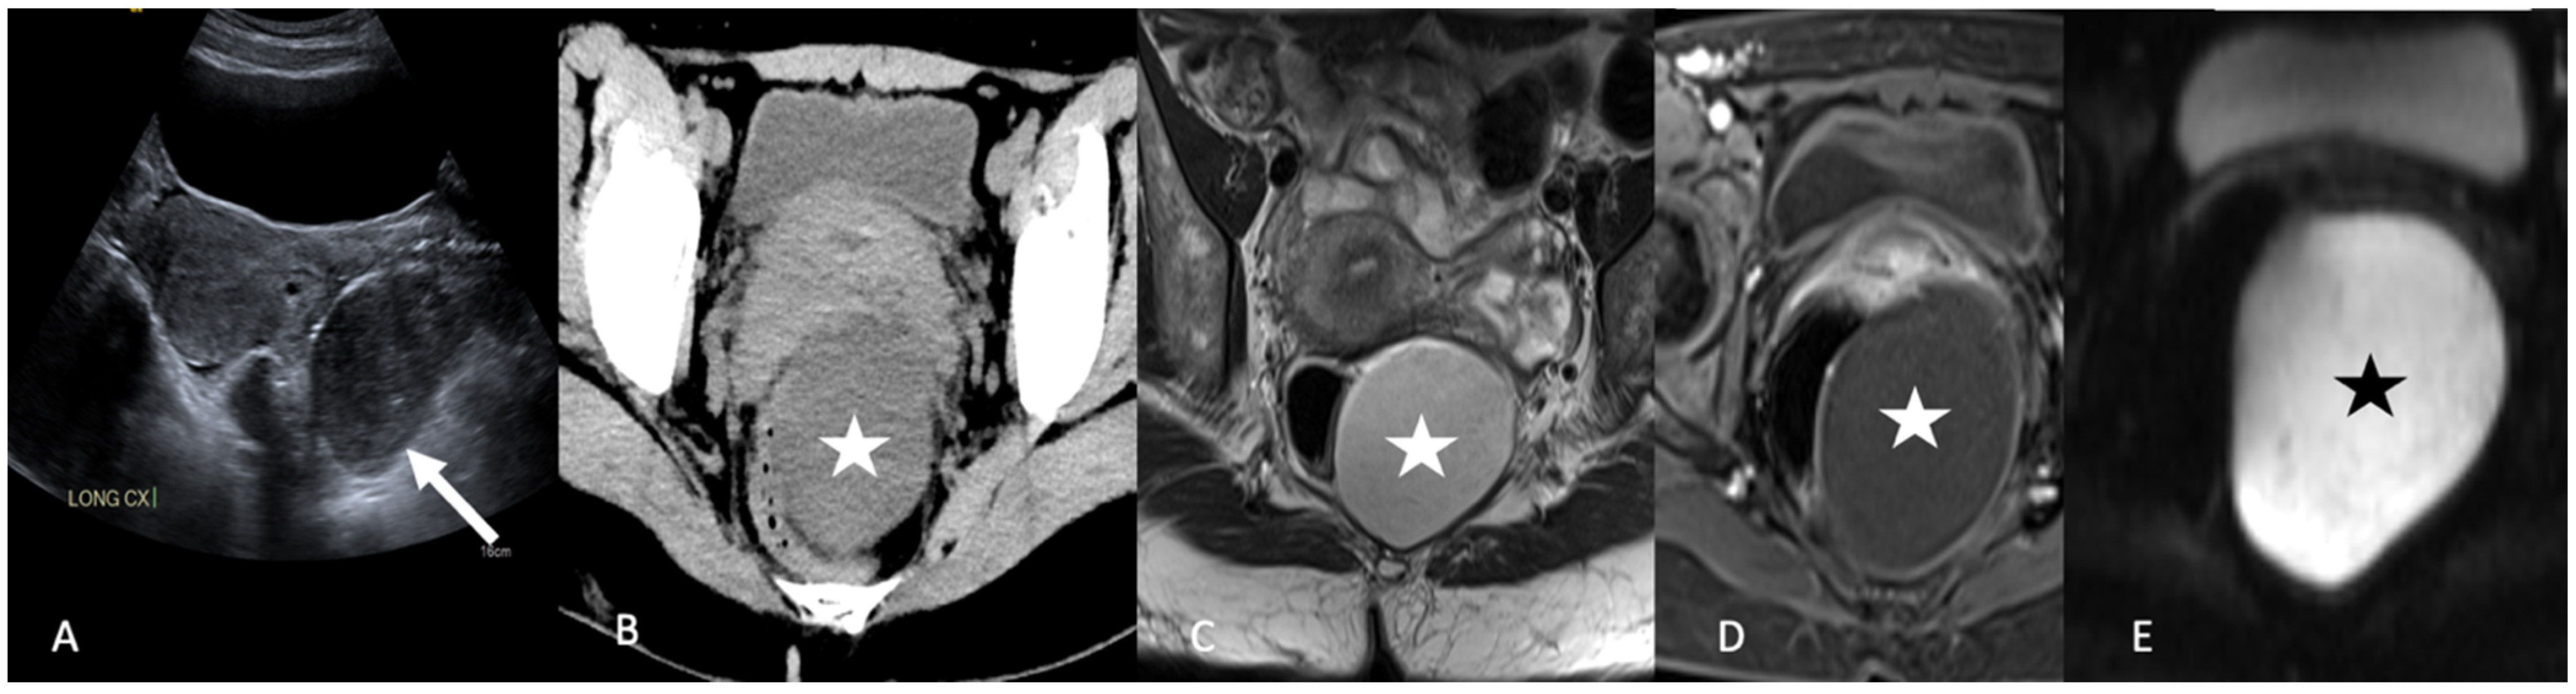

4. Imaging

5.2.2. Leiomyoma

5.3. Peritoneal Disease